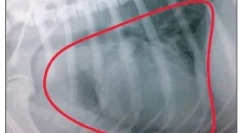

Коскени тумори

Туморите можат да се појават во различни делови на скелетниот мускулен систем - коски, зглобови, екстремитети поврзувачки ткива.